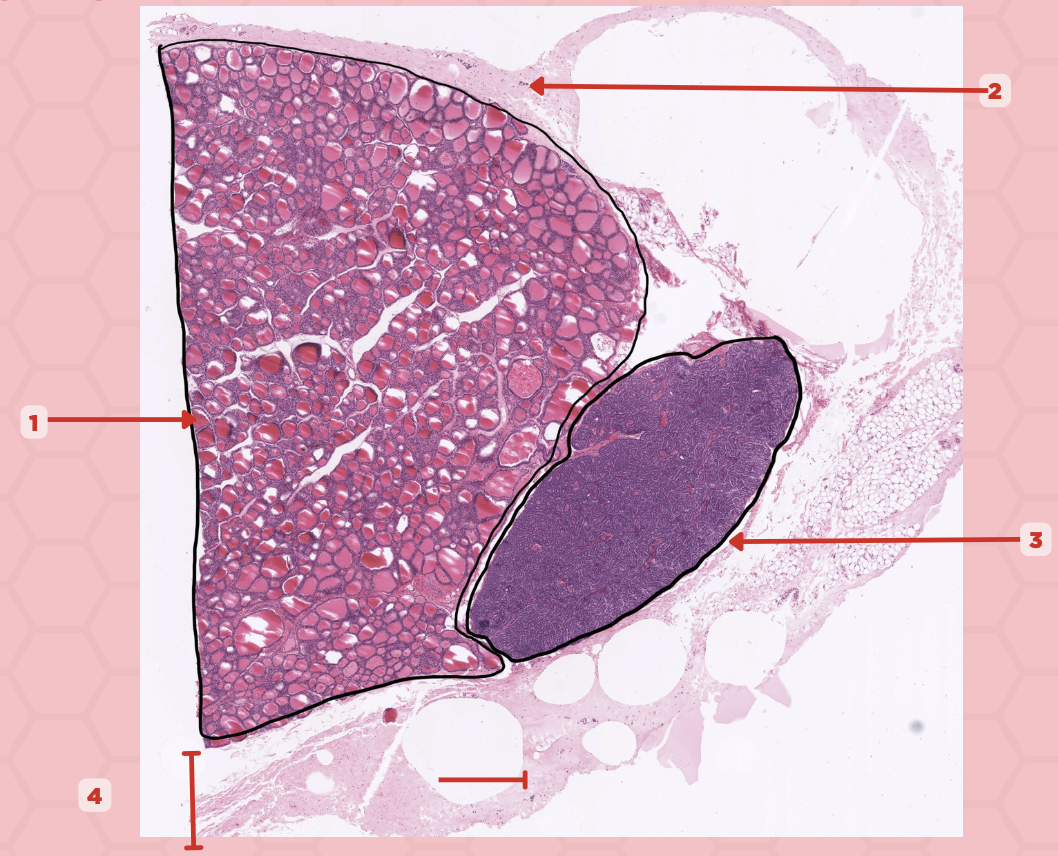

Thyroid-Parathyroid

Identify the specimen.

Thyroid Gland

Identify the structure labeled as 1.

Capsule

Identify the structure labeled as 2 and 4.

Parathyroid Gland

Identify the structure labeled as 3.

Thyroid

Identify the specimen.

Lobules

Identify the structure labeled as 1.

Follicles

Identify the structure labeled as 2.